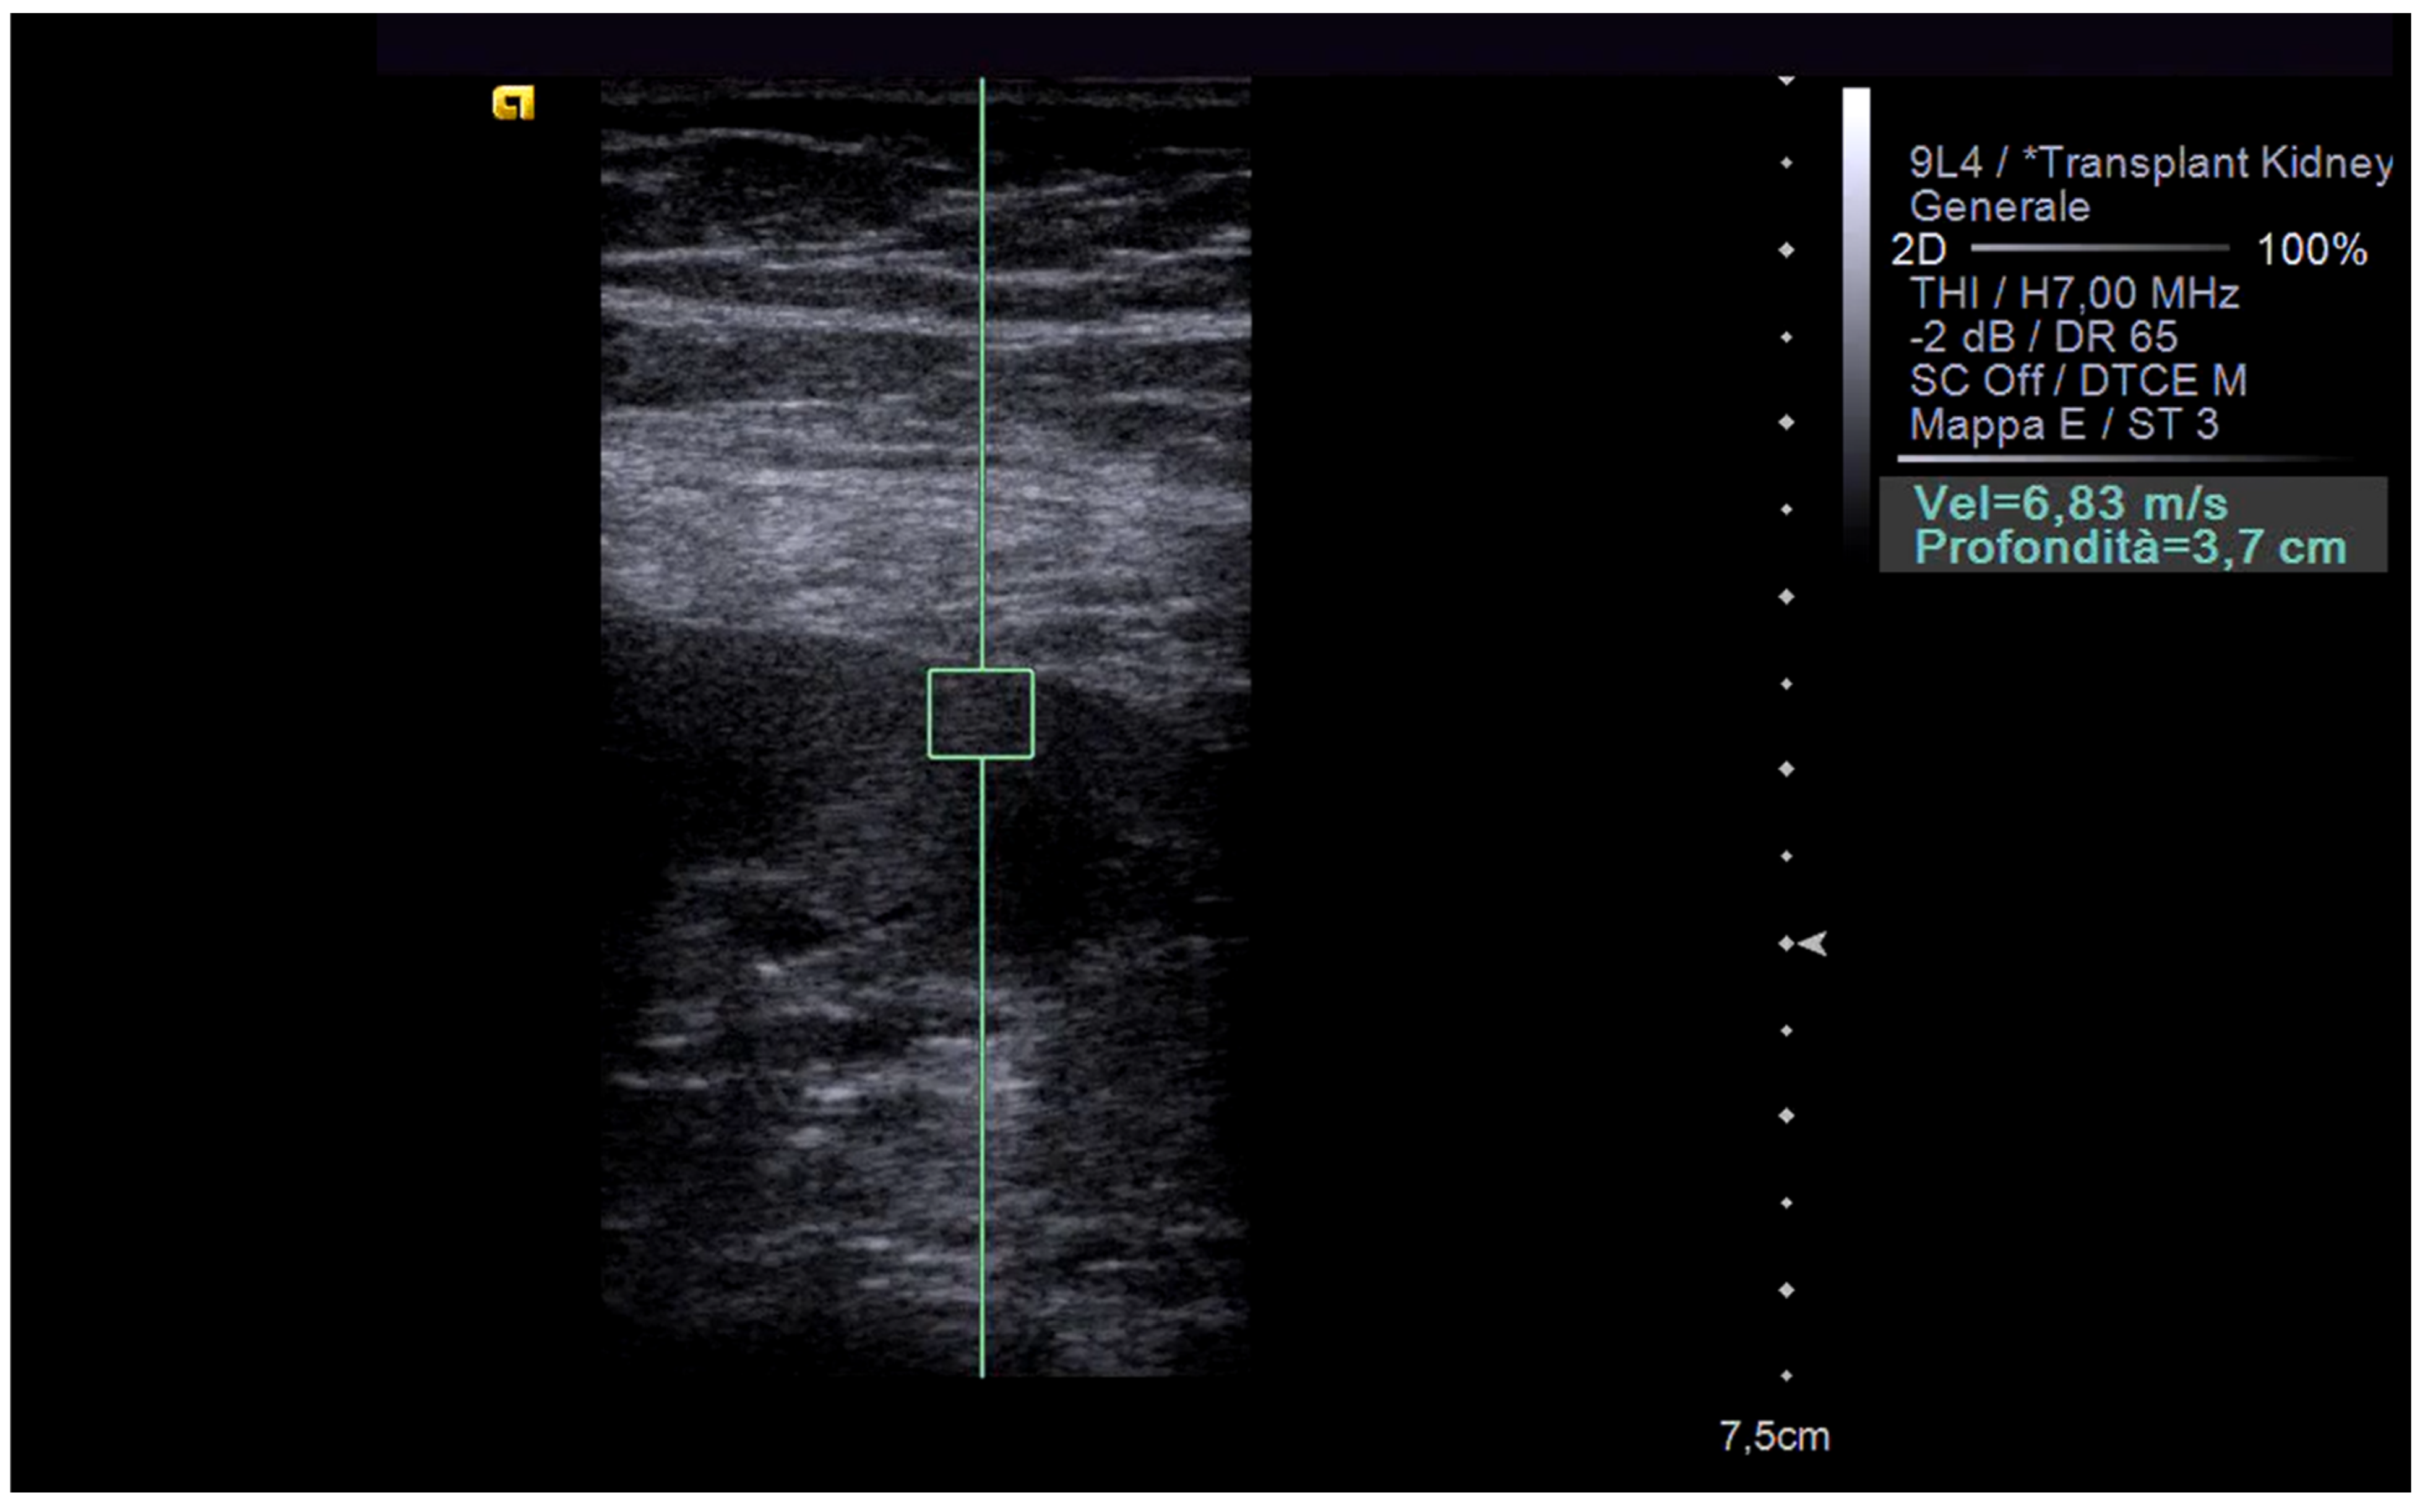

2. Principles of Operation and Comparison of Techniques

3. Elastography in the Kidney: Basic Technique and Limiting Factors